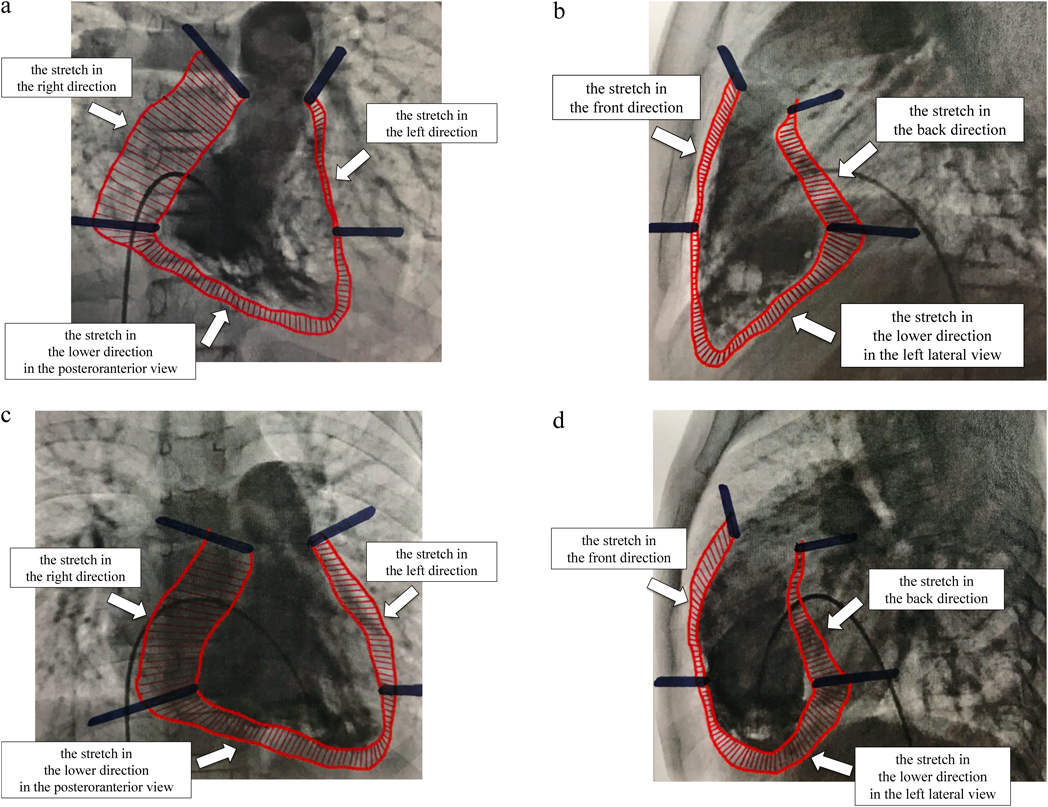

The stretch values were calculated to determine how the right ventricle progressed between systole and diastole (Fig. 2). The stretch values were calculated as follows: We subtracted the right ventricle systolic area from the right ventricle diastolic area in posteroanterior (PA) and left lateral (LL) views on right ventricle angiography and using Cardio Agent analysis software (Toshiba Medical Systems Corporation, Tochigi, Japan). We divided the area into three parts at the position of the tricuspid valve and the position where the line drawn horizontally from the tricuspid valve on the free wall side intersects with the right ventricle. Then, we calculated these areas using ImageJ v1.33, downloaded from the NIH website (http://rsb.info.nih.gov/ij). We corrected the obtained data according to the body surface area (BSA). The stretch was measured in six directions: in the right, lower, and left directions in the PA view; and in the front, lower, and back directions in the LL view. A representative image showing the differences between controls and ASD patients with the crochetage pattern is shown in Fig. 3. Fig. 3a and 3b are control images and 3c and 3d are images showing ASD with crochetage pattern. To ensure the reproducibility of our methods, we examined intraobserver and interobserver differences in stretch values. There was good correlation between intraobserver and interobserver values (r=0.994 and r=0.996, respectively).

Fig. 3 Images of the stretch value

(a) and (b) are control images, and (c) and (d) are ASD with the crochetage pattern images. (a) and (c) are PA views, and (b) and (d) are LL views. ASD, atrial septal defect; LL, left lateral; PA, posteroranterior